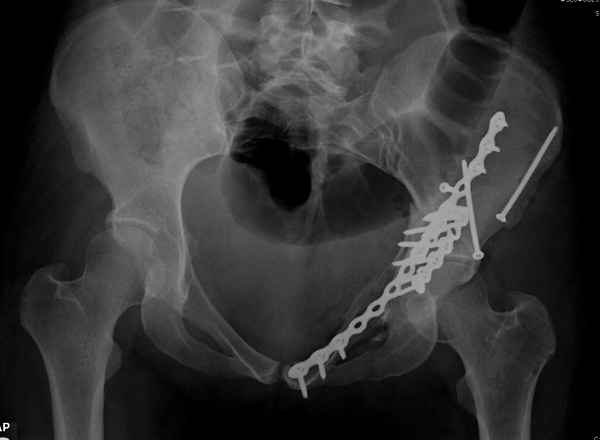

Из того минимума, что представлено, мне кажется, мы имеем дело с двухколонным переломом вертлужной впадины. Обычно медиальный (центральный) "вывих" головки встречаются в сложных двухколонных переломах со смещением.

По-моему, надо готовить больного к будущей артропластике, но без опоры на задний столб невозможно удержать протез. Опорная конструкция (кольца и т.д.) должны иметь опору, и поэтому мы бы сделали реостеосинтез задним доступом. При надобности остеотомия и рутинная фиксация с межколонными винтами.

Здесь несколько вариантов двухколонных свежих переломов, которые были оперированы из одного-заднего, а также из двух: переднего и заднего доступов.